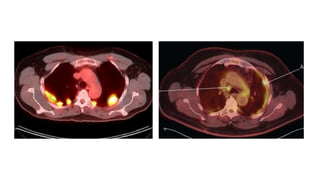

PET-SCAN

• Utilidad para demostrar metástasis extratorácicas y así mejorar la

selección de pacientes para neumonectomía extrapleural.

• Alta eficacia para localizar el mejor punto para realizar la biopsia

pleural ( áreas con un SUV>2).

• El PET- TAC incrementa la sensibilidad diagnóstica en la afectación

mediastínica nodal y es útil como factor pronóstico, ya que una

captación mayor de SUV suele asociar un peor pronóstico.

• Cambia la decisión terapéutica en el 20-40% de los casos.

PET-SCAN • Utilidad parademostrar metástasis extratorácicas y así mejorar la selección de pacientes para neumonectomía extrapleural. • Alta eficacia para localizar el mejor punto para realizar la biopsia pleural ( áreas con un SUV>2). • El PET- TAC incrementa la sensibilidad diagnóstica en la afectación mediastínica nodal y es útil como factor pronóstico, ya que una captación mayor de SUV suele asociar un peor pronóstico. • Cambia la decisión terapéutica en el 20-40% de los casos. Diagnóstico: